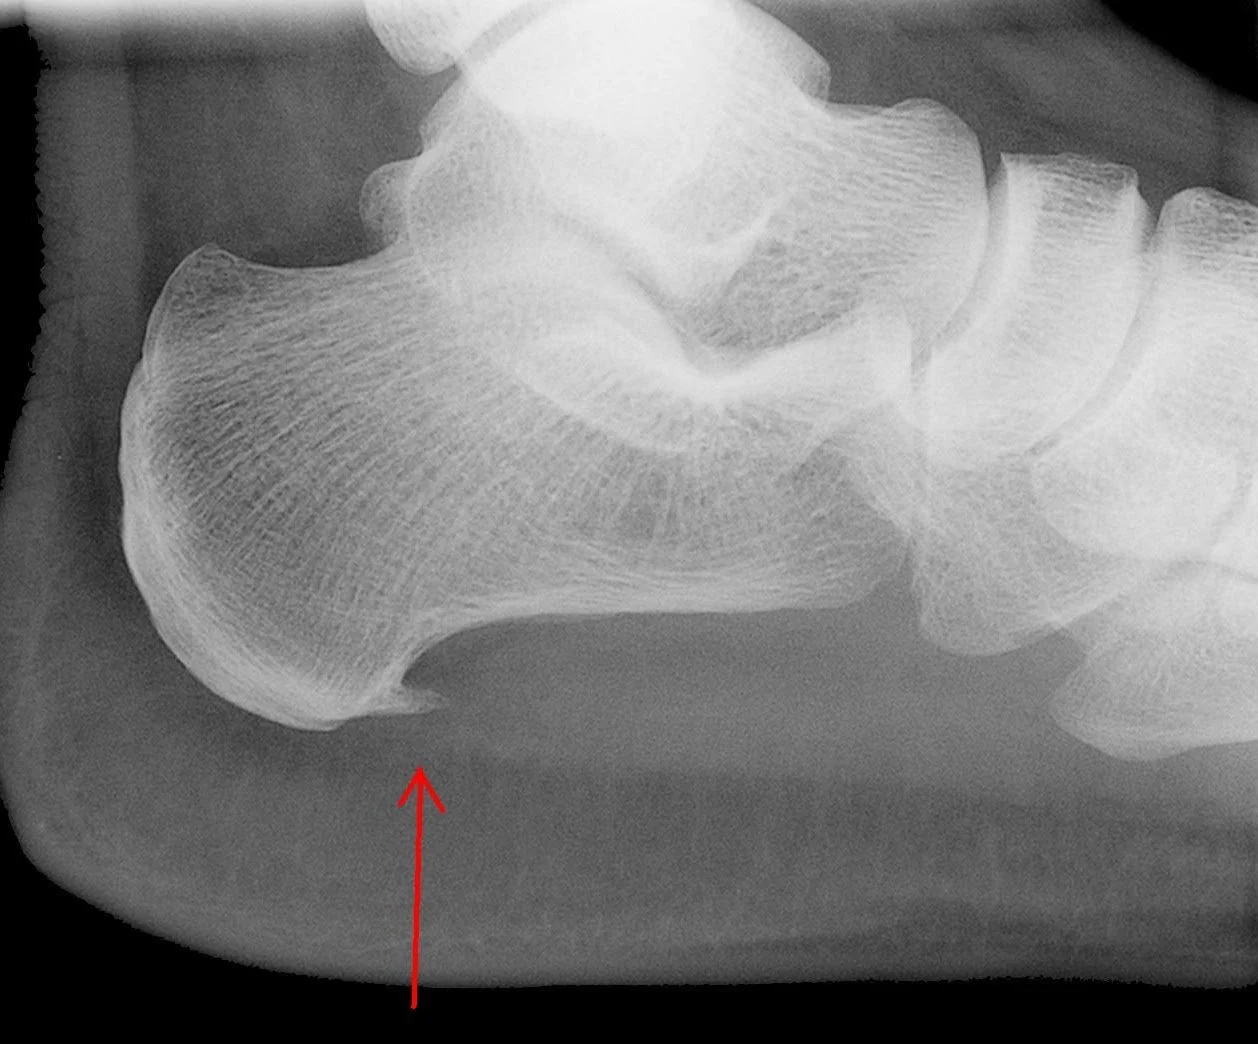

Heel Pain (Plantar Fasciitis)

Inflammation of the tissue along the bottom of the foot. Treatment includes stretching exercises, orthotics, and sometimes injections or surgery.